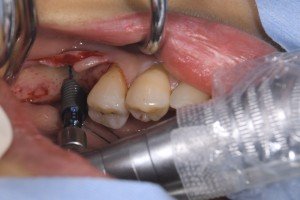

左下の6番部位にストローマンSLActiveロキソリッド4.1Φ12mmを埋入しました。

両側の皮質骨で固定してなるべく長いインプラントを使用します。

大臼歯の単独補綴で咬合力がかなりかかる部位ですが、チタンジルコニア合金素材のロキソリッドであれば問題ないと思います。

使用した、ストローマンボーンレベルインプラントSLActiveロキソリッド RC4,1Φ12mmです。